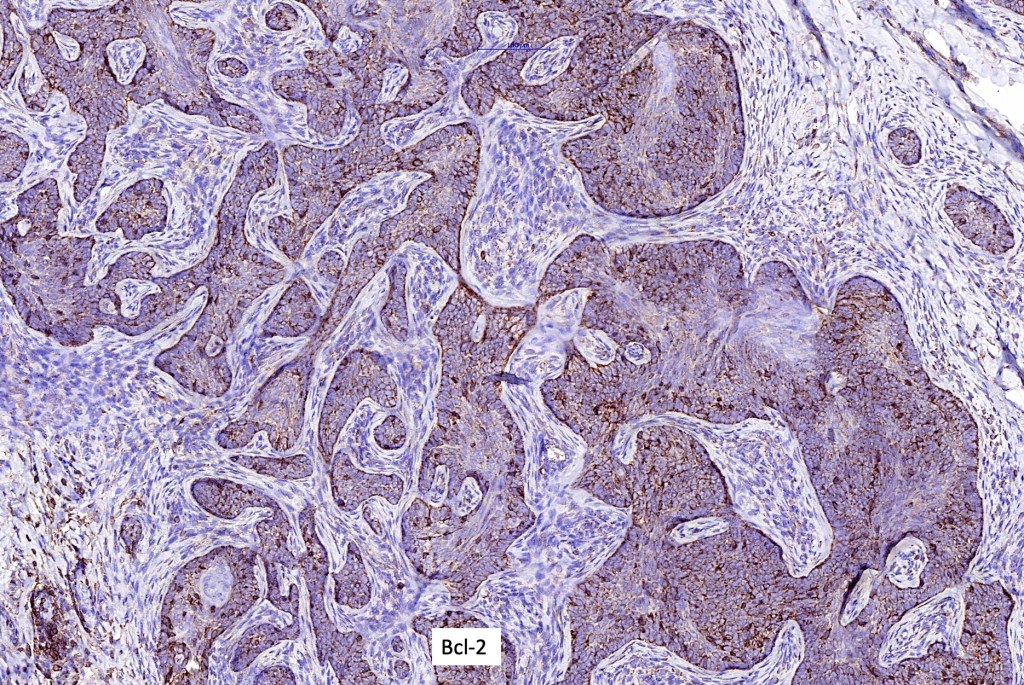

•CK20, PHLDA1 +ve Merkel cells+

•Androgen receptor –ve

•CD10+ (stromal)

•CD34 + (stromal)Bcl2+ve (peripheral)